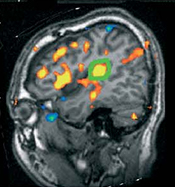

Principle of analgesia